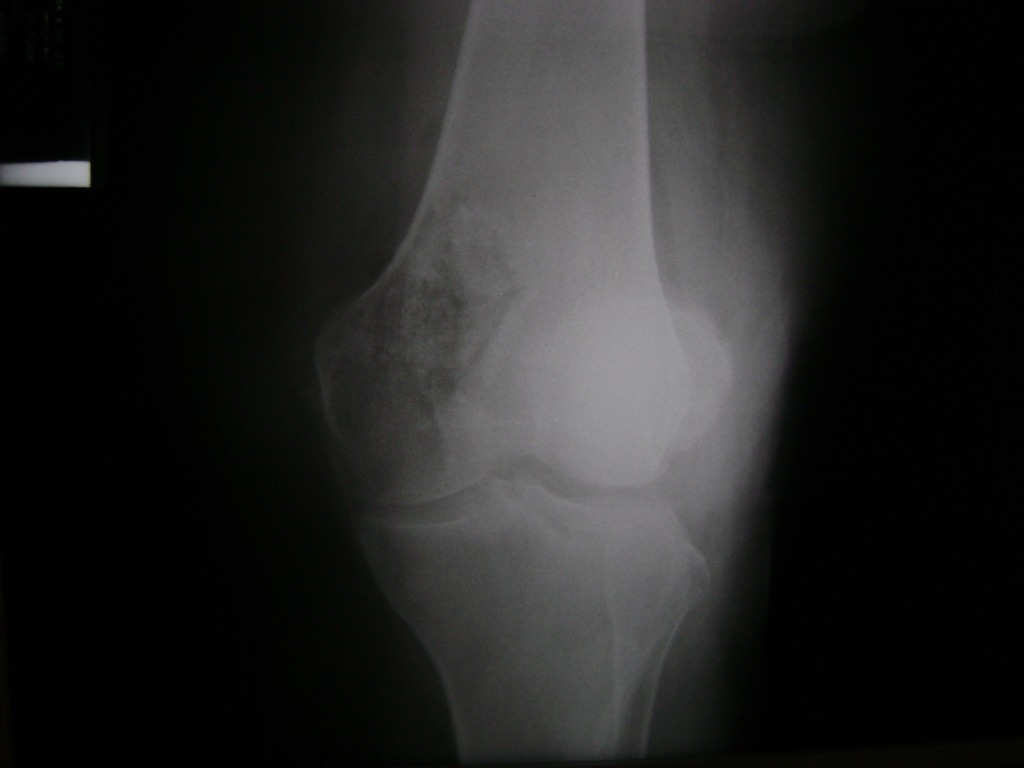

Cirugía de Rodillas